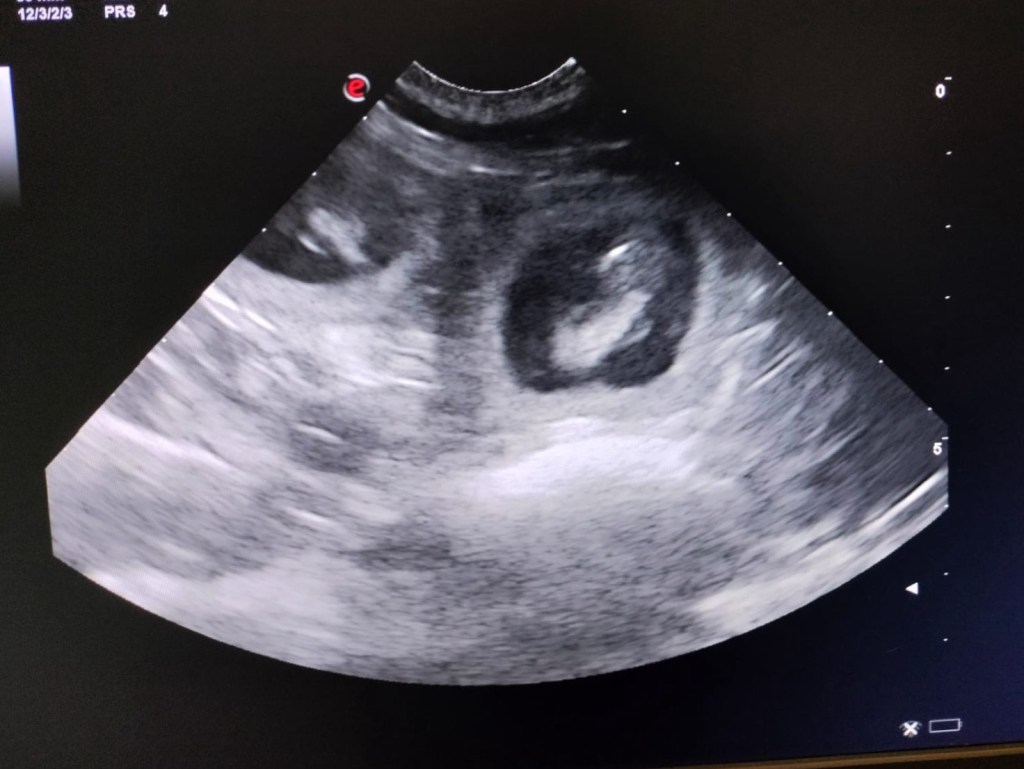

Vrijdag ochtend begon Indy onrustig te worden en werd ik gebeld door Jan – wij waren al op de camping geïnstalleerd zodat ik snel ter plekke kon zijn en ook Yvonne (van Tricksywood’s kennel) was direct onderweg. Samen met Jan en Alie hebben we Indy de hele dag bijgestaan en konden we de nacht in met een paar gezonde pups in de werpkist. Indy moest hard werken want de pups waren erg sterk en goed op gewicht – het duurde daarom eventjes om ze uit te drijven en we waren met z’n allen ook erg moe na de lange dag en nacht maar heel trots te kunnen mededelen dat er 7 prachtige en levendige pups zijn geboren – 4 teven en 3 reuen. Gefeliciteerd Jan en Alie met dit prachtige nest.

Moeders en pups maken het heel goed. Indy is een geweldige moeder – vanaf het eerste moment super zorgzaam alsof ze nooit anders heeft gedaan. Heel bijzonder om te zien en ook wat ik verwacht had van deze knappe dame. Ze heeft echt een fantastisch karakter – eigenlijk is ze qua temperament en persoonlijkheid de ideale Flatcoat. Ze heeft meer kwaliteiten dan dat natuurlijk – maar wat valt mij dit nu op. Ik ben een beetje verliefd op Kaspar z’n vriendin geloof ik.. Kaspar had een hele andere nacht – hij kon de luie camping prins uithangen:

Early Friday morning Jan called me out of bed that Indy was getting restless and I rushed to their home alongside with Yvonne (from Tricksywood’s kennel) we came to assist Jan & Alie. Indy delivered her first puppy at 2100 hrs and we had a long day and night to finally have a beautiful litter of 7 lively and strong puppies: 4 bitches and 3 males. All are black. Big congratulations to Jan & Alie.

Indy is a perfect mother – from the first moment on she takes very well care of the pups. What a wonderful girl she is 😍.

Jan en ik zijn zoetjes aan begonnen met de voorbereidingen voor het C nest. Alle puppy spullen zijn nu verhuist naar Brabant en komende week ga ik lekker bij Indy & Jan op bezoek zodat we alles opgelijnd hebben voor de geboorte. Ik kijk er heel erg naar uit. Volgens Jan is er veel buikactie en geniet hij samen met Arie en de kleinkinderen van de vooruitzichten van een zomer vol puppies.

Jan and I have started preparing the upcoming litter – all our puppy stuff has temporarily moved to Brabant and next week we have a pre-birth check up at Jan’s place. I am looking forward seeing Indy and her belly again. According to Jan there is full stomach action and they are enjoying the anticipation of a puppy full summer.